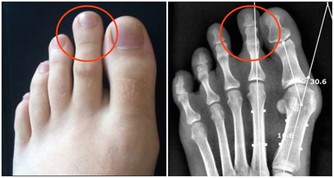

髖關節炎是另一種常見的胯骨疼痛原因,發生率隨著年齡增加而升高。它屬於一種慢性退化性關節疾病,主要表現為髖關節軟骨變薄、磨損,最終導致骨性關節炎。

關節炎發生的關鍵環節是軟骨細胞受到機械性壓力及發炎因子的長期作用,導致軟骨矩陣蛋白降解多於合成,軟骨層逐漸磨薄。

這使得骨頭直接互相摩擦,刺激受壓骨膜出現增生性改變,患者在運動時會感到壓痛不適。

隨著軟骨變薄,關節活動範圍也逐漸限制,嚴重時可完全喪失功能。X光檢查可見關節間隙變窄、骨贅形成。而且病灶還多累及胯骨內側。在治療方面,臨床可採用物理治療、適度運動等保守治療。對於晚期嚴重者可選擇人工關節置換手術。

預防髖關節炎的關鍵在於保護關節。為此要合理控制體重,改善姿勢,不扭動胯部。同時適量運動也有助關節營養和延緩退化。中老年人也應多補充維生素C、鈣質等,延緩軟骨破壞過程。否則最終可能需承受手術風險及復原痛苦。